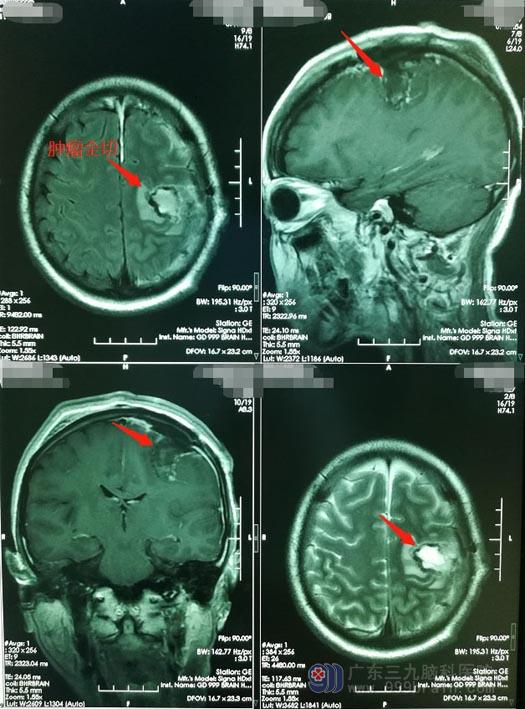

在阿兰夫妻及医护团队的密切配合下,神经外五科医生团队为患者实施了“唤醒麻醉下左侧额叶占位切除术”,手术完成顺利。术后第三天,阿兰神志清楚,对答正确,能够遵嘱活动,右手抓握能力改善,未出现任何不良症状。术后磁共振提示:肿瘤全切。

▲手术后